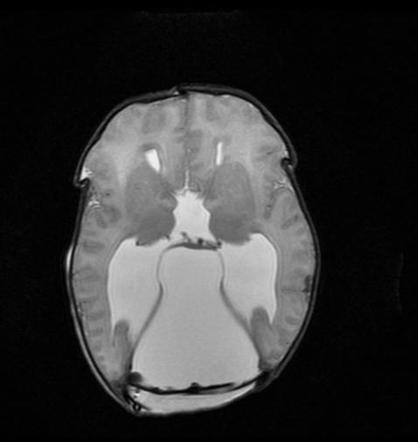

МРТ снимки мальформации Денди-Уокера